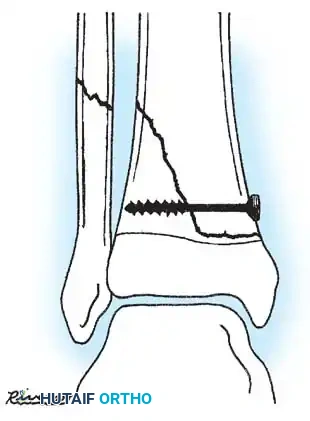

These tuberosity-extending fractures are not simple avulsions; they are massive, tongue-type Salter-Harris III injuries that lift the entire tibial tuberosity and anterior proximal physis superiorly. They almost universally necessitate open reduction and internal fixation (ORIF) to restore joint congruity and extensor mechanism continuity.

Fig. 33-175: Fixation of a tongue-type Salter-Harris III fracture utilizing cancellous screws.

5. Fixation:

* For vertical fracture components, insert transverse guide pins.

* In older children and adolescents nearing skeletal maturity, utilize 4.0mm or 4.5mm partially threaded cancellous bone screws to achieve interfragmentary compression.

* In younger children with significant remaining growth potential, utilize smooth Kirschner wires (K-wires) placed transversely or horizontally to minimize the risk of physeal arrest.